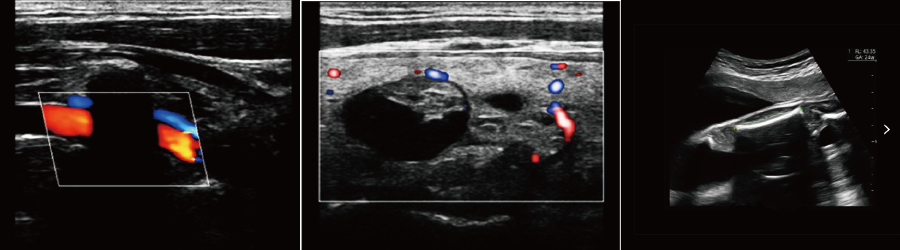

便攜式彩超機(jī)

●IMT血管內(nèi)中膜自動測量

●血流M(MC)成像

強(qiáng)大的功能和豐富的測量軟件,迅速而便捷地幫助您解決腹部、外周血管,婦科,產(chǎn)科,新生兒和小兒科,骨骼肌肉,心臟等各種臨床診斷的需要;